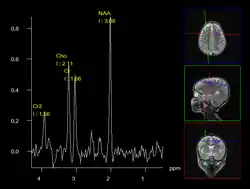

A less intrusive alternative imaging technique is magnetic resonance spectroscopy (MRS), which is used to determine the chemical compositions of cells. However, it is not as reliable as biopsies.[12]